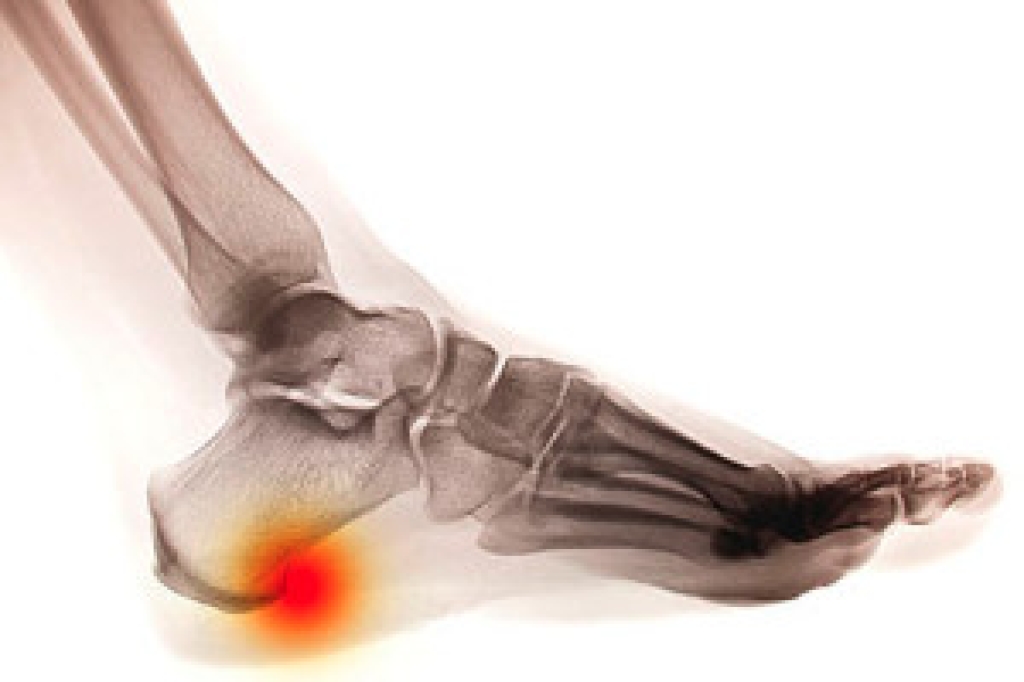

The majority of foot conditions are common and can be treated by a podiatrist. Standard diagnostic procedures are generally used to identify specific conditions and treatment can be rendered. A podiatrist also treats rare foot conditions which can be difficult to diagnose and may need extra attention and care.

A podiatrist can properly diagnose and treat all types of rare foot conditions. If your child is affected by any of these symptoms or conditions, please don’t hesitate to call our office so the correct treatment method can begin.